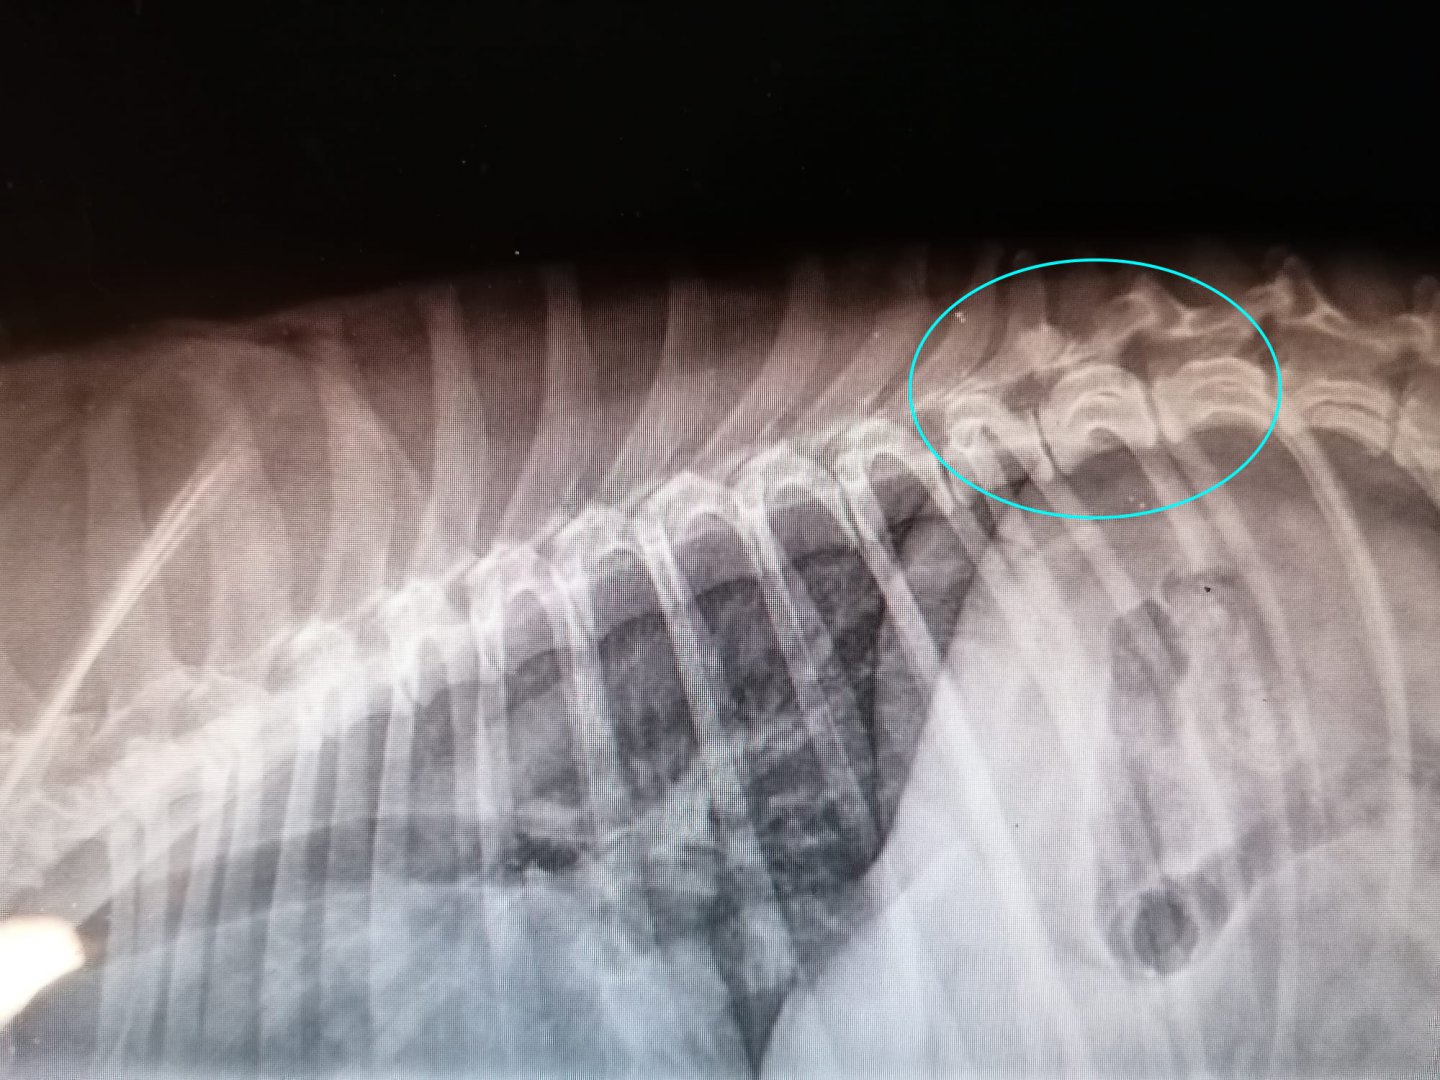

Ik bel maandagochtend meteen naar mijn dierenarts. Ik mag met Boden gaan om 13u voor uitgebreid onderzoek. Het onderzoek wijst uit: gevoelig aan de rug, net bij het einde van de ribbenkast. RX laat uiteindelijk zien dat L1 waarschijnlijk ooit gebroken is geweest. Een aangeboren afwijking sluit de dierenarts uit, het lijkt trauma te zijn. Nu zit er ontsteking rond dat oude letsel. Dit kan hem een intense pijnscheut, zenuwpijn, hebben opgeleverd waarbij hij heeft gereageerd op het eerste het beste wat het dichtst bij hem stond. Doordat ik zijn achterpoten heb opgeheven, heb ik hem, ongewild en onbewust, waarschijnlijk extra pijn gedaan. Daarom ook dat hij niet losliet en pardoes omverviel. Daarom ook dat Brooklyn hem meteen had vergeven. Ze wist ook dat dit niet normaal was voor hem, haar beschermer in normale omstandigheden.